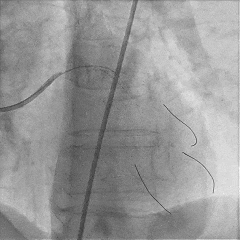

处理RCA病变:

Runthrough导丝至RCA远端,预扩球囊扩张RCA近中段病变处

植入支架Tivoli 2.75*18mm一枚

高压球囊后扩张后,无残余狭窄,血流TIMI3级

双侧造影,观察闭塞起始位置、长度、走行等